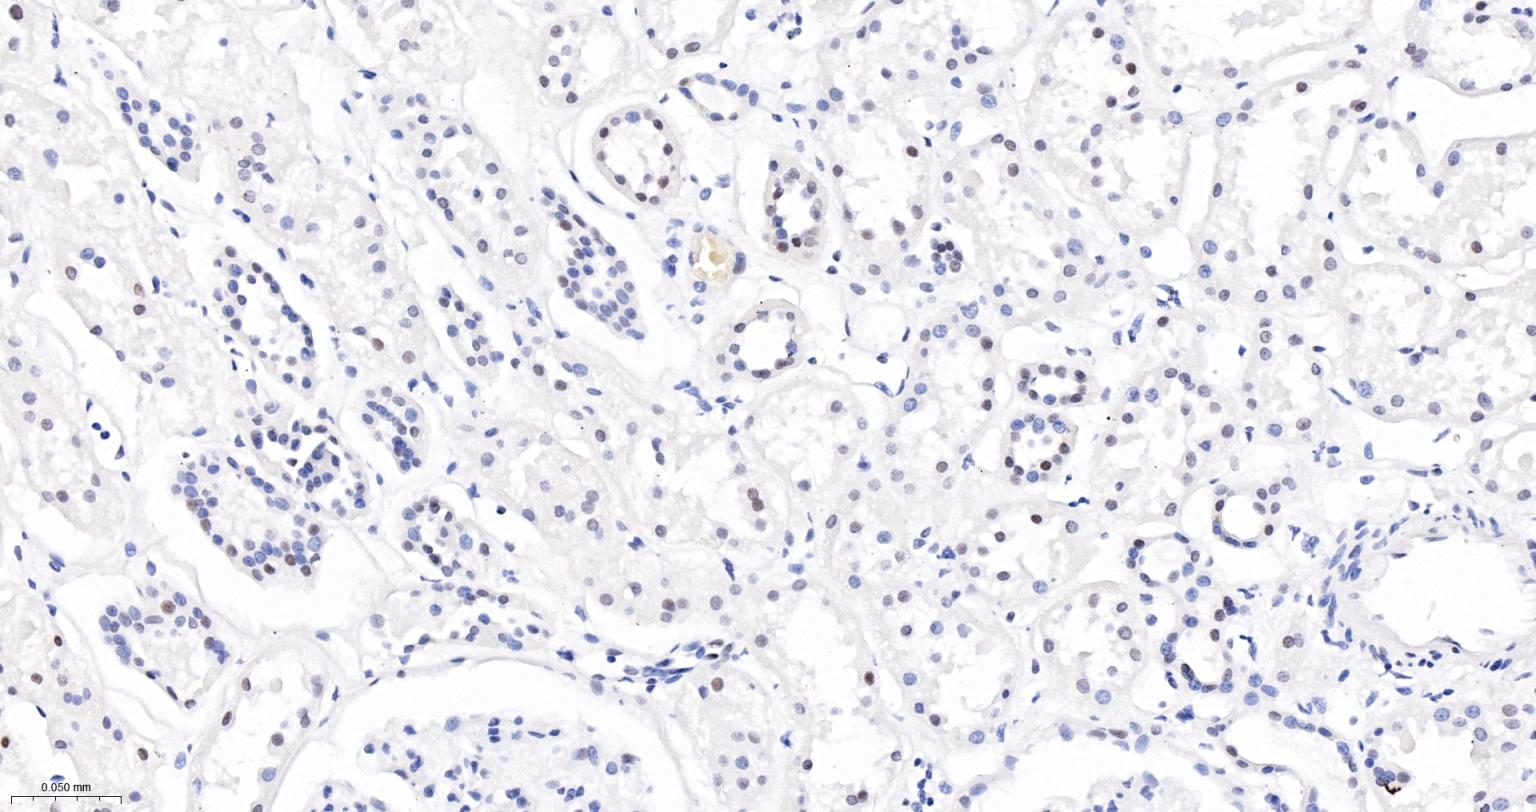

Paraformaldehyde-fixed, paraffin embedded Human Kidney; Antigen retrieval by boiling in sodium citrate buffer (pH6.0) for 15 min; The section was incubated with USP39 Monoclonal Antibody, Unconjugated (bsm-63016R) at 1:200 overnight at 4°C, followed by conjugation to the bs-0295G-HRP and DAB (C-0010) staining.